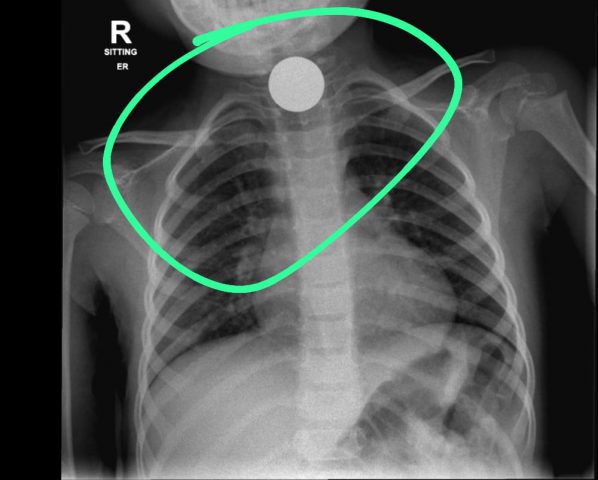

מיום שבת הובאו אל המחלקה לרפואת ילדים בבית החולים אסותא, ארבעה ילדים בני 7, 4, 10 ו-6 כשהם סובלים מאי שקט ומהקאות. בבדיקות שנעשו התגלה בצילומי הרנטגן כי ארבעתם סובלים מבליעה של עצמים זרים. הילדים בלעו בין היתר חלקי משחק, מגנטים, שרשראות ושניים בלעו מטבעות כסף של 10 אגורות.

בחלק מהמקרים הילדים שוחררו לביתם לאחר מספר שעות, אך חלקם הוכנסו לחדר ניתוח. בצילומי רנטגן שנעשו בילדה בת 7, התגלה כי חלקי המשחק שבלעה התיישבו במעי ולאחר שעות רבות בהם לא הצליחו לטפל במצב היא הוכנסה לחדר ניתוח בו הוציאו את החלק שנבלע. במקרה של בת ה-4 המטבע שבלעה גרם לחסימה חלקית ודחיקה של קנה הנשימה, דבר שמנע ממנה לנשום כראוי ולכן היא הוכנסה לחדר ניתוח גם כן. נציין כי הניתוחים עברו בשלום והילדים הועברו להמשך התאוששות בבית החולים.